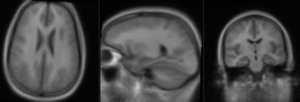

Slicer Registration Library Case #10: group atlas to structural MRI

This is an example of inter-subject registration; we seek to align a group atlas image with a structural reference T1. Approach: we first compute an affine alignment of the atlas to the T1. We then proceed to nonrigid registrations of higher and higher DOF, stopping at the DOF where deformations become unreasonable. We can constrain the deformation by either explicit limits on the absolute deformation amount or via a mask. Constraints become increasingly critical as DOF increases.

Registration Results

RegLib C10 unregistered.png unregistered (click to enlarge)

RegLib C10 registered1 Affine.png after affine registration (click to enlarge)

RegLib C10 registered2 Affine.gif after affine registration (click to enlarge)

RegLib C10 registered3 BSpline.gif after nonrigid BSpline (5x5x3) registration (click to enlarge)

RegLib C10 registered4 BSpline2.gif after nonrigid BSpline (7x7x5) registration (click to enlarge)